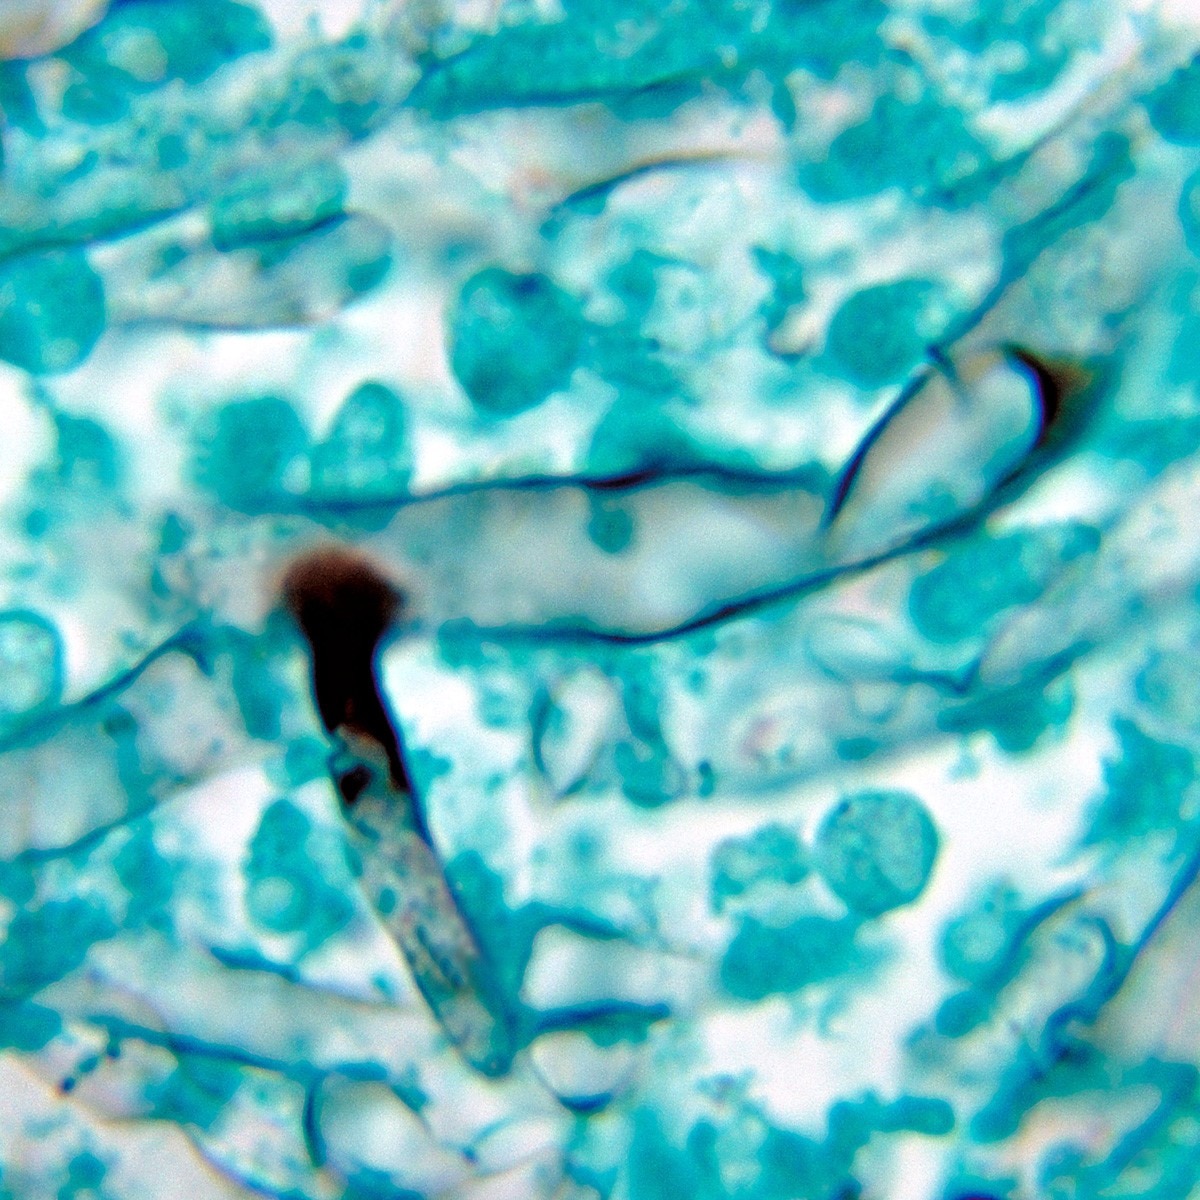

प्रतीकात्मक फोटो (Getty)